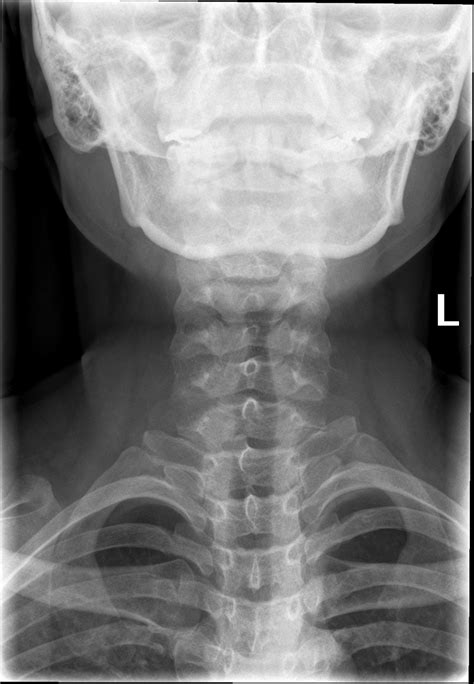

A Soft Tissue Neck Xray is a medical imaging technique that uses low-dose X-rays to produce images of the soft tissues in the neck region. Unlike traditional X-rays that focus on bones, a soft tissue X-ray is designed to visualize structures such as muscles, tendons, and ligaments. This makes it an invaluable tool for diagnosing conditions that do not involve bone abnormalities.

Interpreting the results of a Soft Tissue Neck Xray requires expertise in radiology. The radiologist will examine the images for any abnormalities, such as:

A Soft Tissue Neck Xray can help diagnose a variety of conditions, including: